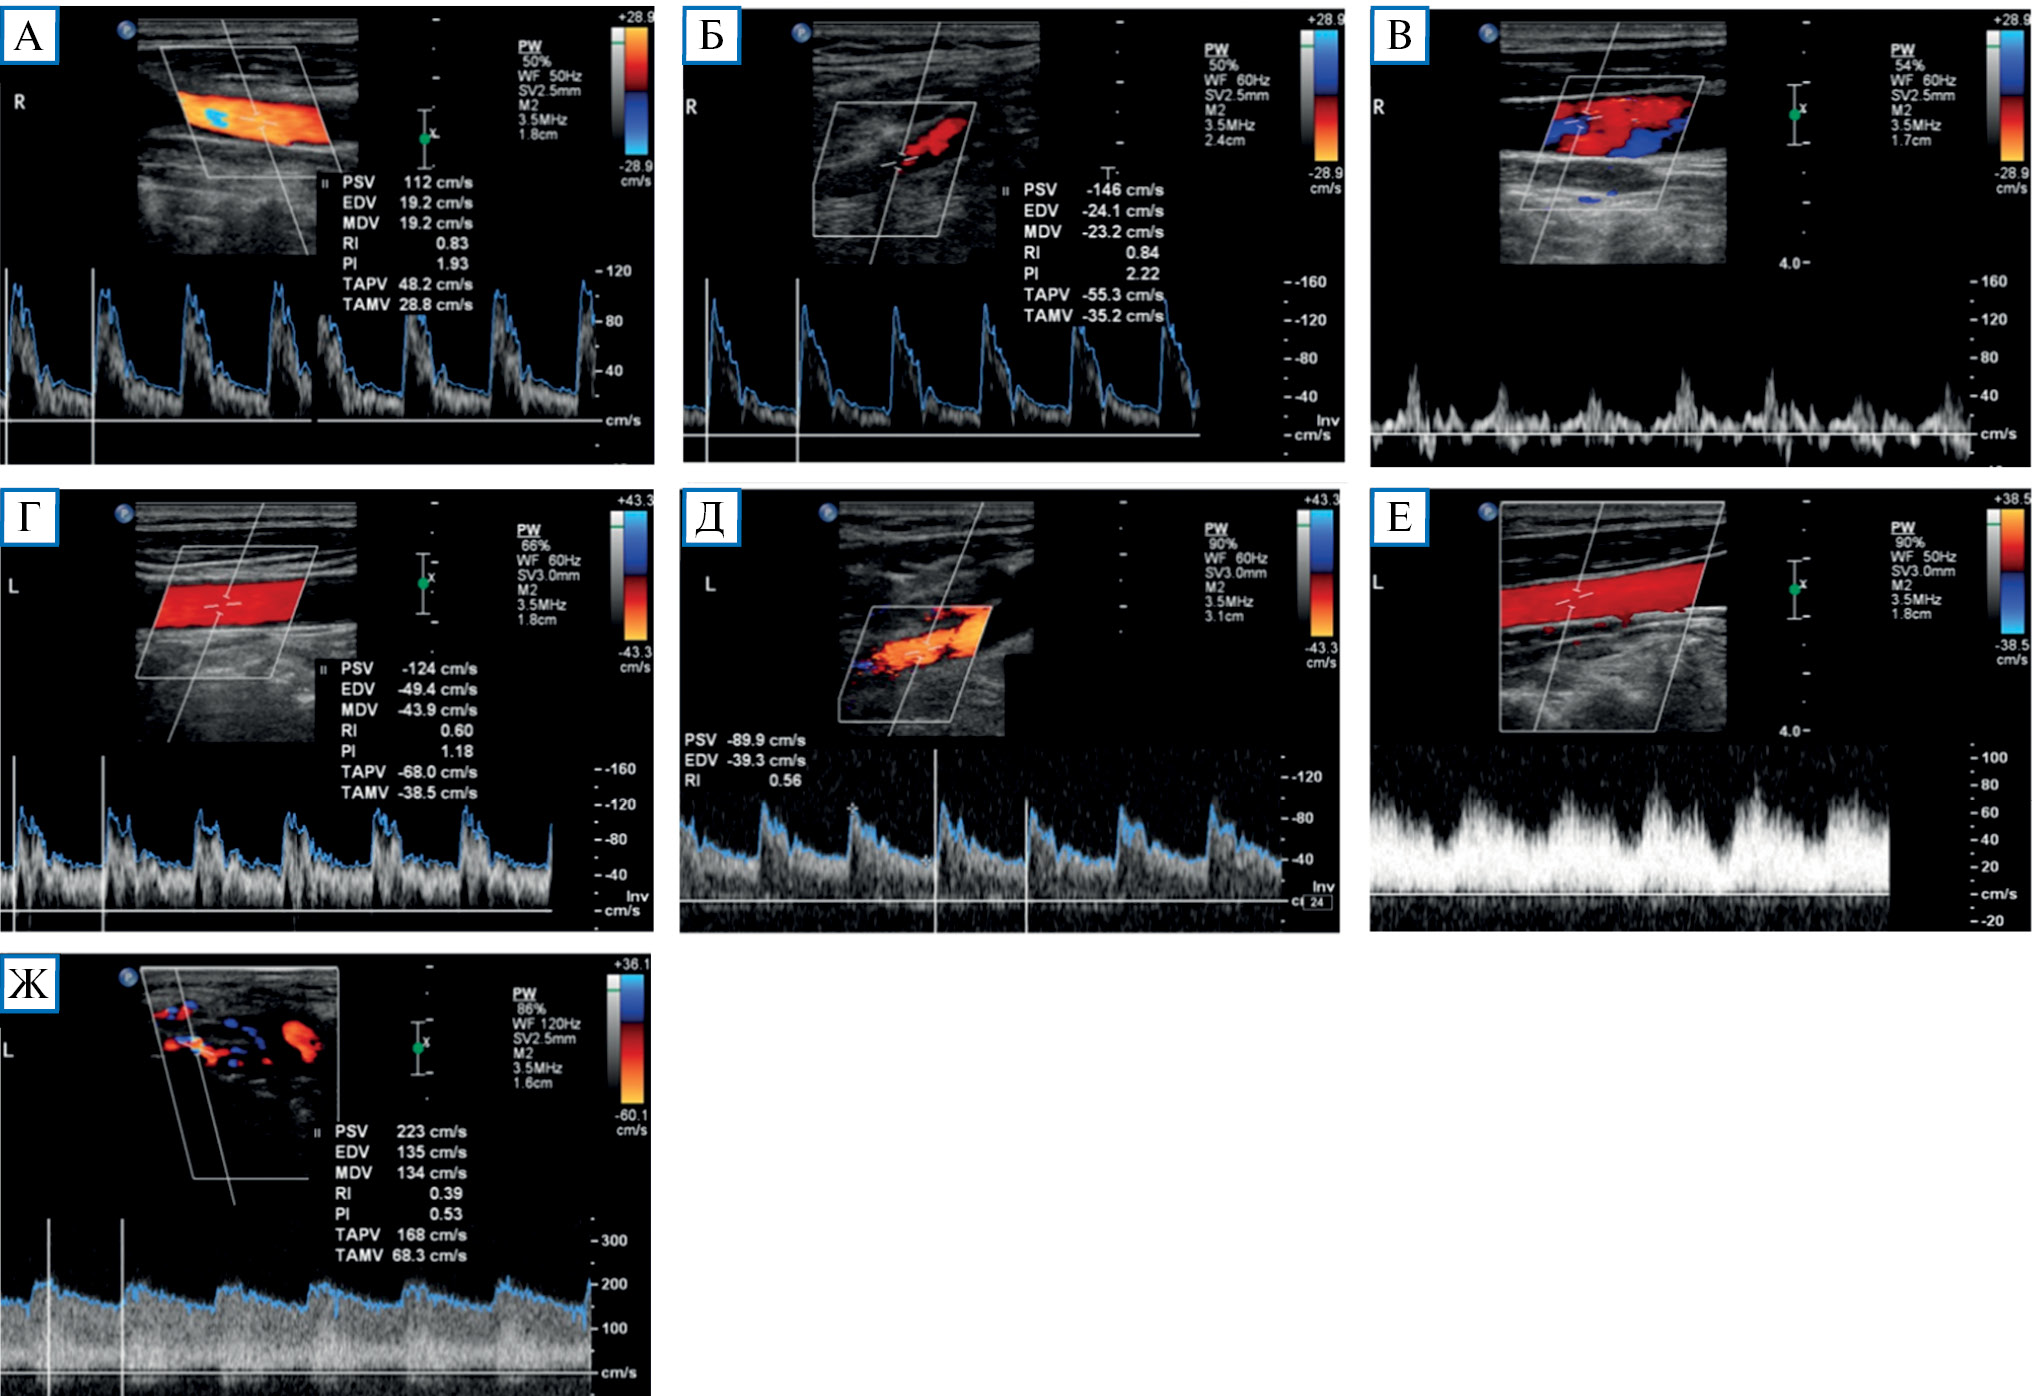

Проведенное дуплексное сканирование сосудов головы обнаружило признаки артериовенозной мальформации в бассейне левой наружной сонной артерии с артериализацией и усилением кровотока по внутренней яремной вене. Усиление скорости кровотока по задней околоушной артерии позволило предположить ее в качестве «питающего» сосуда (рис. 1). Контрастная МР-ангиография подтвердила наличие артериовенозного соустья с вовлечением поперечного и частично сигмовидного синусов слева (рис. 2).

Рис. 1. Дуплексное сканирование сосудов шеи

Примечание. Кровоток по общей сонной артерии (А) и наружной сонной артерии (Б) справа с нормальными индексами периферического сопротивления (PI и RI). Физиологический трехфазный кровоток по правой внутренней яремной вене (В). Кровоток по общей сонной артерии (Г) и наружной сонной артерии (Д) слева со сниженными индексами периферического сопротивления. Артериализация кровотока по левой внутренней яремной вене (Е). Значительно повышенный кровоток с низкими индексами периферического сопротивления по задней околоушной артерии (ветви наружной сонной артерии) в области артериовенозной мальформации (Ж).